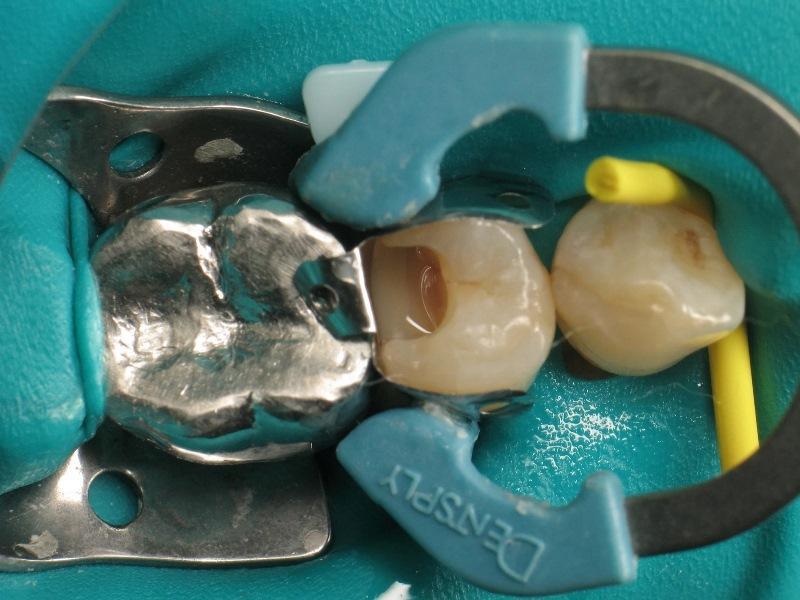

Фото 3: Полость после удаление кариозных тканей.

Фото 4: Установка проксимальной матрицы.